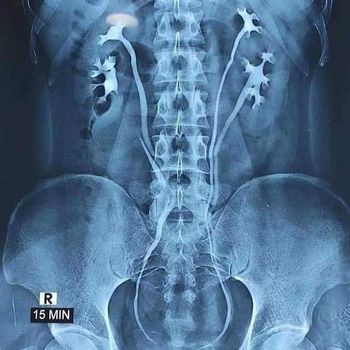

Viral postingan foto X-Ray menunjukkan seseorang memiliki empat ginjal. Foto: Tangkapan layar viral |

Ramai penampakan hasil rontgen yang menunjukkan seseorang memiliki empat ginjal. Fenomena langka itu mendadak disorot warganet.

"Kondisi medis yang langka, seorang pria menemukan bahwa dia memiliki empat ginjal di tubuhnya," tulis postingan viral.

Dikutip dari The Guardian, ahli bedah Niaz Ahmad, menilai sangat mungkin seseorang memiliki empat ginjal. Kondisi ini biasanya disebut 'duplex kidneys', ginjal terbelah menjadi dua saat kandungan memasuki trimester pertama.

Kondisi ini juga membuat ginjal terbelah hanya sebagian atau menumbuhkan ureter kedua yakni tabung yang mengalirkan urine ke kandung kemih. Kondisi lain yang dapat menyebabkan seseorang memiliki struktur ginjal hingga empat kali lipat jumlah normal adalah penyakit ginjal polikistik.

"Sangat jarang ada ginjal tambahan lengkap. Mungkin hanya dialami satu dari satu juta orang," kata Niaz Ahmad.